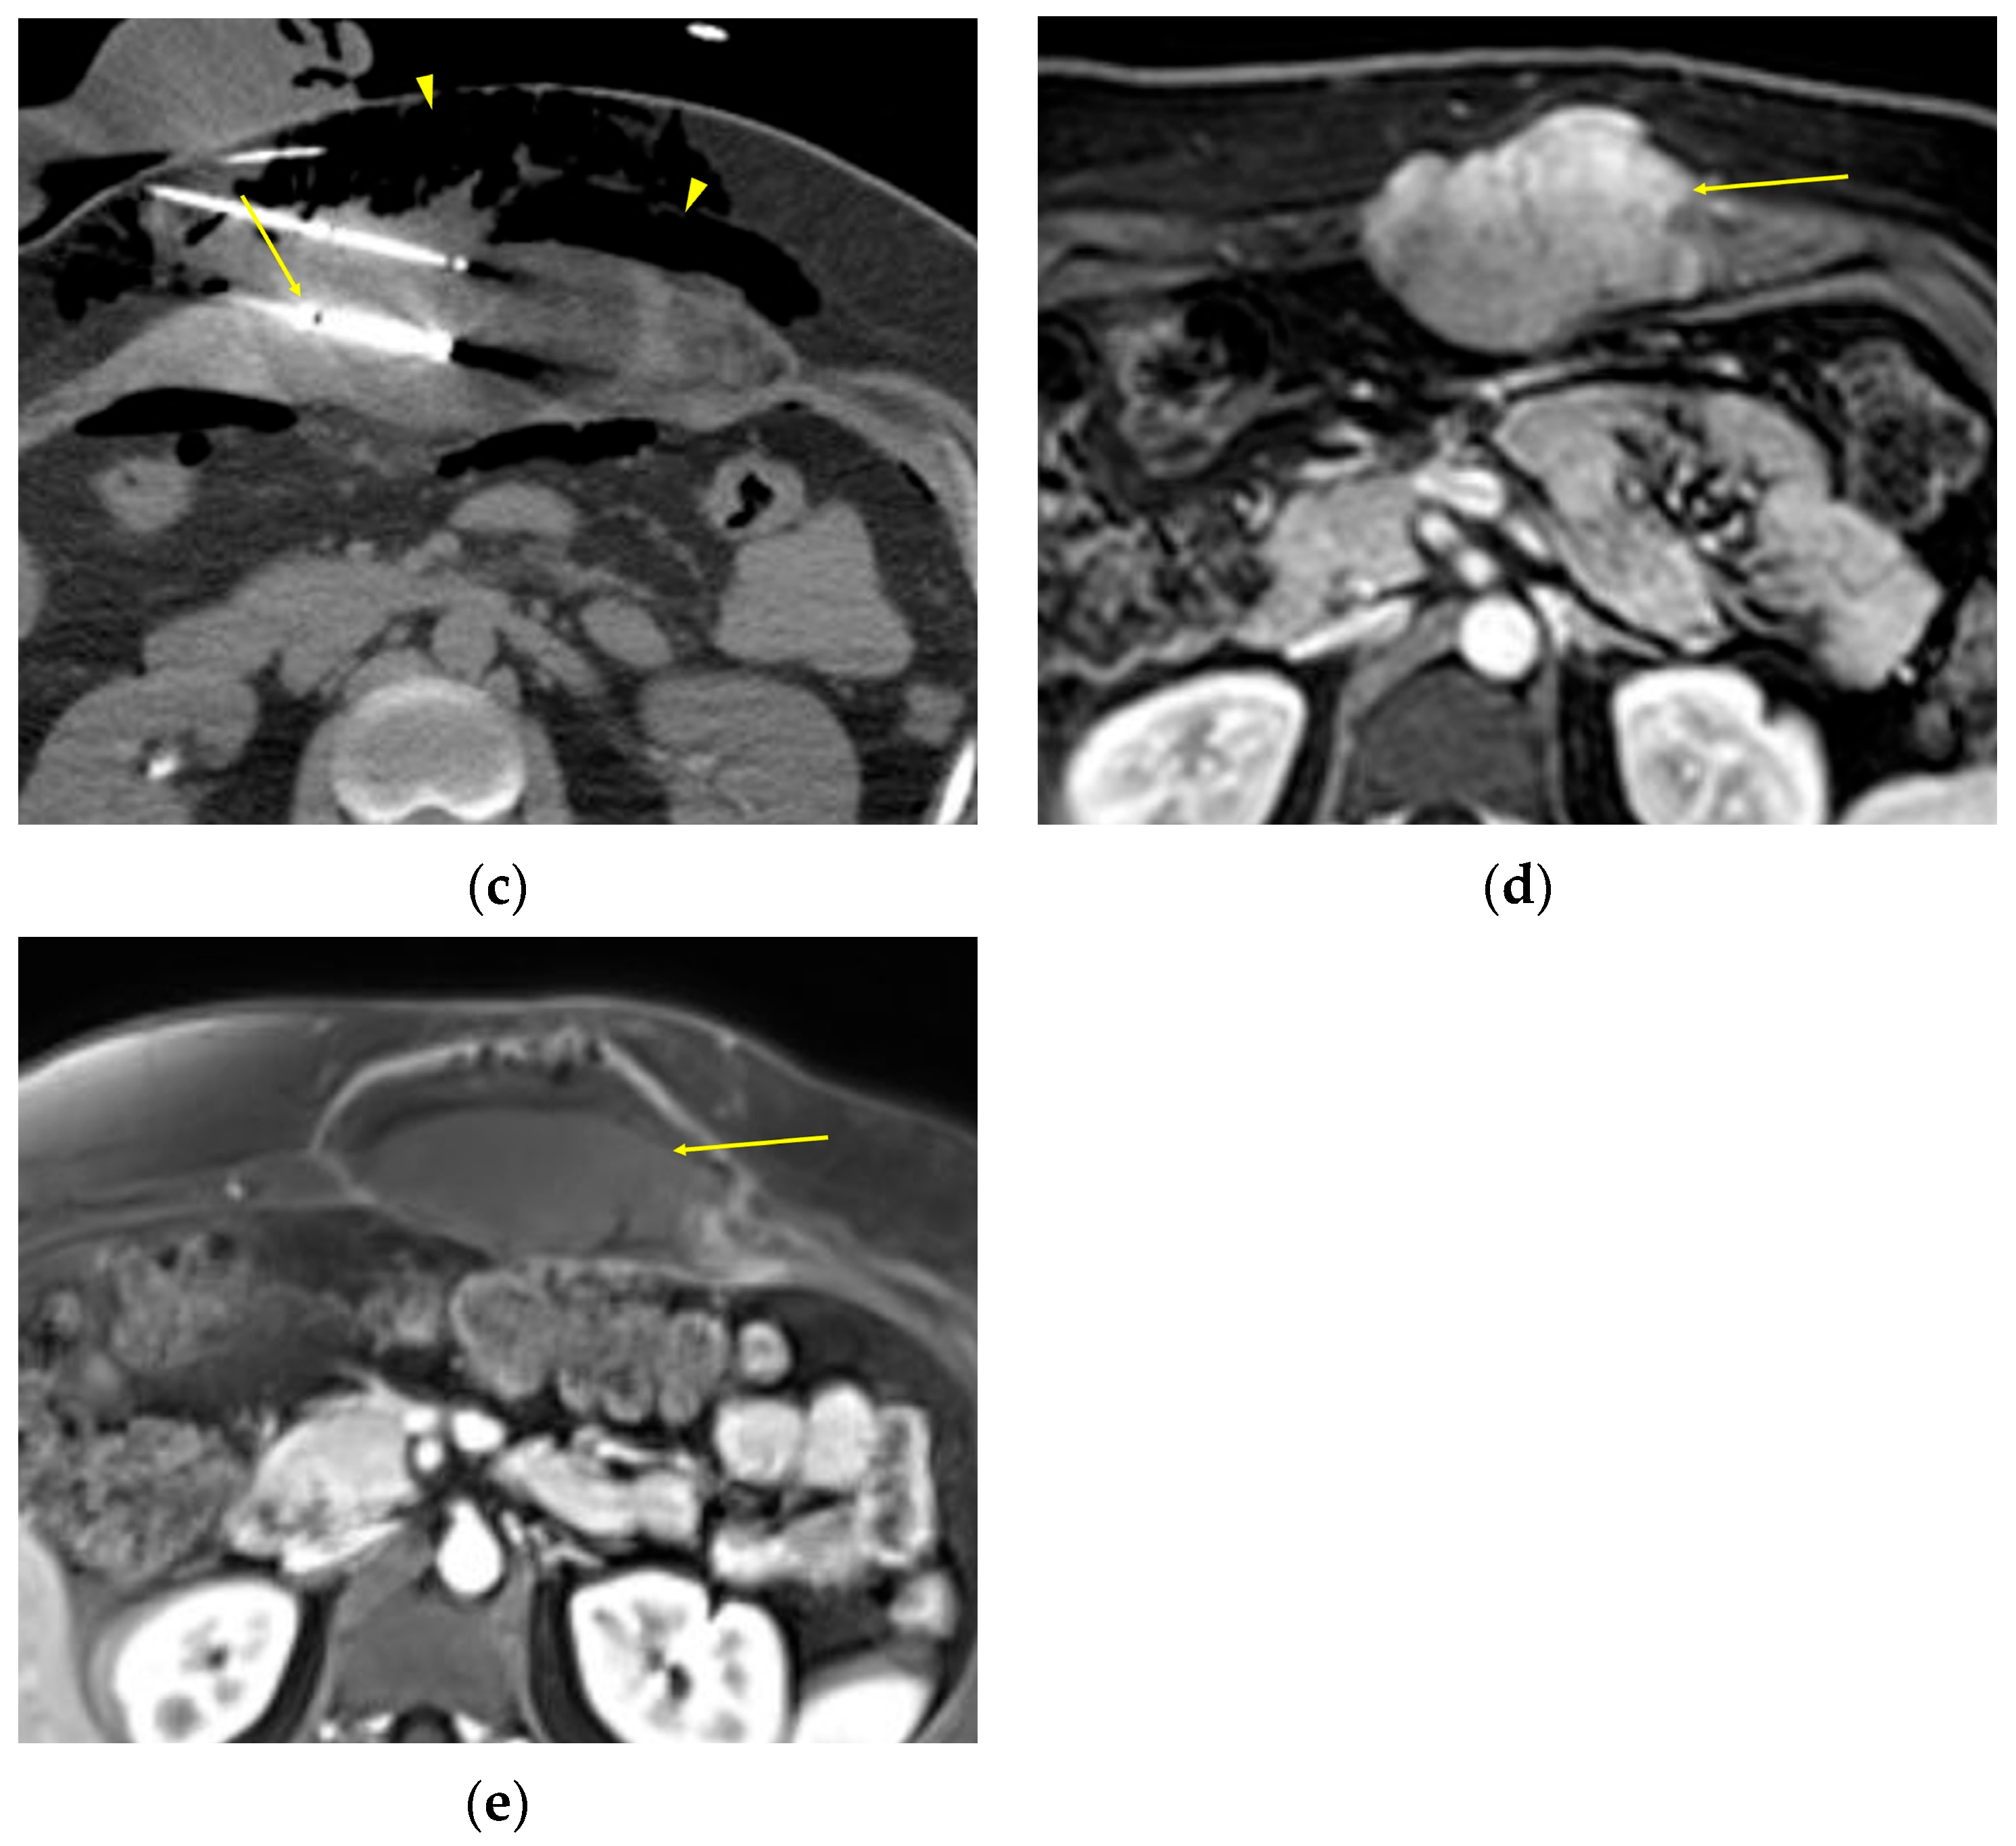

| MRI | Well-circumscribed, heterogenous with nonenhancing T1/T2 hypointense curvilinear areas related to collagen, and T1 intermediate to low/T2 intermediate to high areas related to cellularity or the myxoid matrix. Additional secondary signs (“flame”, “staghorn”, “fascial tail”, etc.) are described in text. |

- Kurtz, J.E.; Buy, X.; Deschamps, F.; Sauleau, E.; Bouhamama, A.; Toulmonde, M.; Honoré, C.; Bertucci, F.; Brahmi, M.; Chevreau, C.; et al. CRYODESMO-O1: A Prospective, Open Phase II Study of Cryoablation in Desmoid Tumour Patients Progressing after Medical Treatment. Eur. J. Cancer 2021, 143, 78–87. [Google Scholar] [CrossRef]